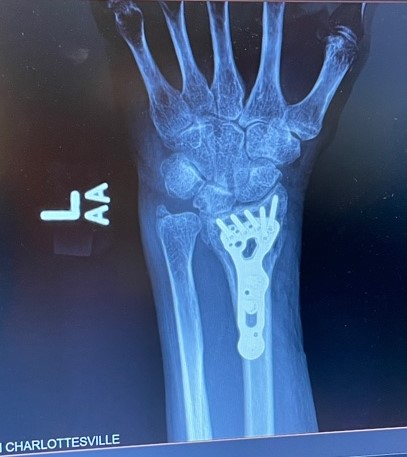

OUCH!